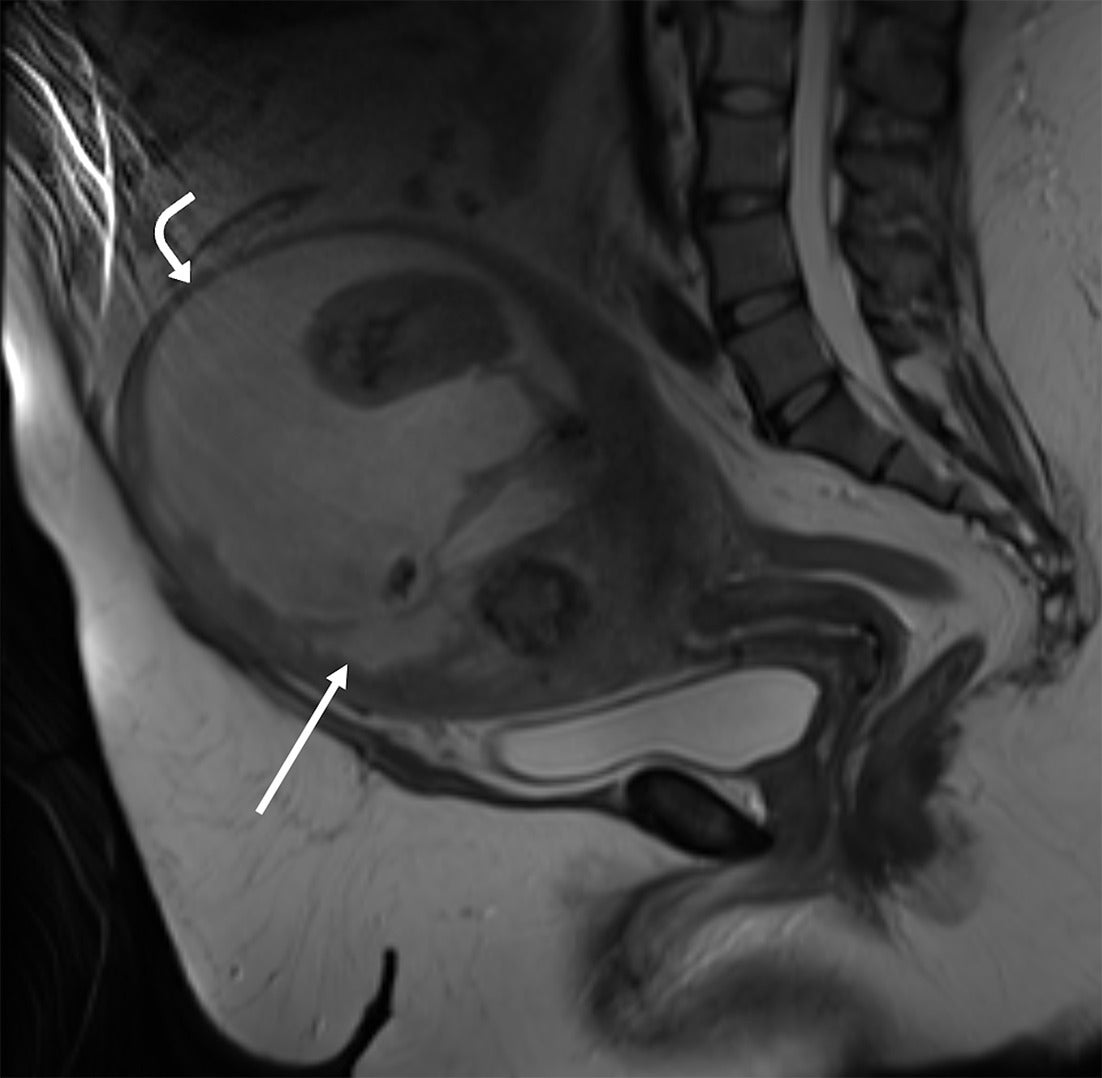

Abdominopelvic CT with intravenous contrast performed upon initial presentation showed a lobular enlarged uterus with a centrally necrotic, partially calcified intramural uterine fibroid at the uterine fundus, which contained a small locule of gas along the anterior myometrial mantle ( Figure 1 ). A subsequent MRI of the pelvis was performed without intravenous contrast and demonstrated similar findings ( Figure 2 ).

Sagittal T2-weighted MRI of the pelvis without intravenous contrast shows an enlarged uterus with a large, heterogeneous necrotic myometrial mass with cystic, solid, and calcified components (straight arrow). The small locule of gas visualized on the CT was not visualized at the time of MRI. There is marked myometrial thinning along the anterior and superior margins of the necrotic mass (curved arrow).